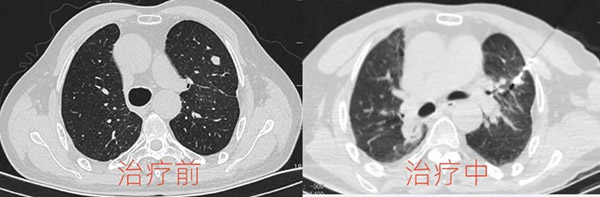

患者于先生两年前因右肺癌行右肺上叶切除术,2024年2月在复查肺CT时,发现左肺上叶出现结节,大小约13mm*9mm,而且边界欠清,这让于先生及家属产生了严重的心理负担:“再做手术或者放化疗,身体真的吃不消啊!”

最后,在征得患者和家属同意后,于3月2日下午,肿瘤介入科团队于CT定位下为于先生顺利实施了左肺结节微波消融术,手术很成功,于先生激动地说:“一根小针就能使肺结节在几分钟内消失,还恢复得这么快,真是太神奇了,为咱们十院肿瘤介入科的医生点赞!”